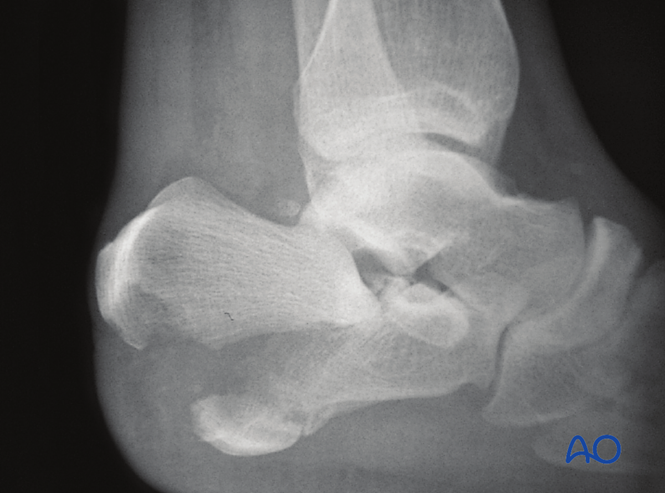

鸟嘴样骨折(Beak fracture,又名喙状骨折)

这种罕见的移位性跟骨骨折可为关节内或关节外。其最重要特征是伴随严重的软组织损伤及潜在软组织并发症。由于后方软组织显著破坏,若入院时尚未表现为开放性骨折,后侧皮肤内部压力将迅速导致皮肤破裂,转变为开放性骨折。

此类骨折由强壮的跟腱(Achilles tendon)撕脱后侧骨块引起,骨块可能位于关节内或外。偶见完全关节外骨折,但仍需相同的手术复位治疗。若未准确复位,将因跟腱功能障碍导致肌力减弱。

图示为开放性关节内鸟嘴样骨折,需紧急手术复位以保护软组织并恢复关节对位。